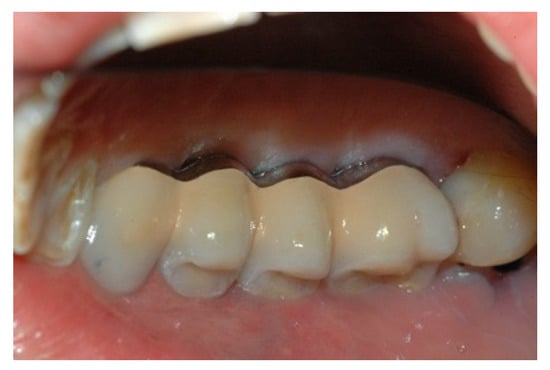

When the prosthesis was positioned, the mesostructure was fixed by tightening the screws with a torque wrench at 30 Ncm, and the superstructure was cemented by carrying out a radiographic check to evaluate the structural coherence (Figure 12, Figure 13 and Figure 14).

Figure 12. Cementing the superstructure.

Prosthesis 02 00023 g012

Figure 13. Cementing the superstructure.

Prosthesis 02 00023 g013

Figure 14. Cementing the superstructure.